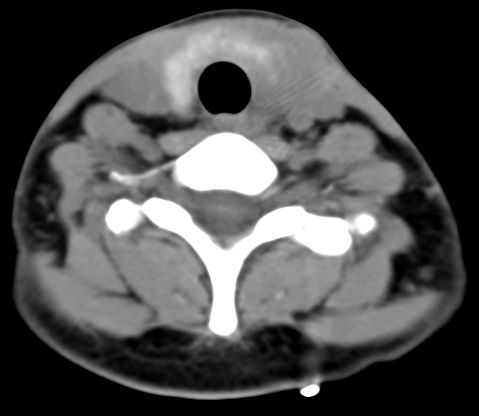

标题: CT9717:F、30Y、颈部左侧包块半年,压痛.患者拒绝作增强。 [打印本页]

标题: CT9717:F、30Y、颈部左侧包块半年,压痛.患者拒绝作增强。

请各位老师帮忙看看左侧甲状腺病灶!

甲状腺弥漫增大,以左叶明显,内见不均匀低密度影,边缘模糊欠清,周围脂肪间隙模糊。

结合病史:考虑亚急性甲状腺炎可能性大。(不知道病人有没有检测tsh t3 t4)

左侧甲状腺及甲状腺狭部弥漫性增大,边缘模糊,未见明确界线.考虑甲状腺炎可能性大.

甲状腺弥漫增大,以左叶明显,左侧内见不均匀低密度影,边缘模糊欠清,周围脂肪间隙模糊。

1,病灶弥漫无明确边界.2,密度较均质.3,临床压痛明显.

2,亚急性甲状腺炎.临床多见,发病年龄较轻,由上呼吸道感染或病毒性腮腺炎后发病.临床触痛明显.然局部皮肤无红热.t3t4早期升高,后期降低.病灶可单侧或双侧.易炎性渗出,使脂肪密度增高.